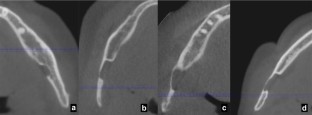

Fig. 1